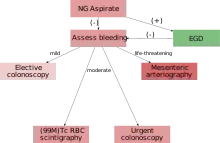

Diagnostic evaluation must be performed after patients have been adequately resuscitated. If an upper GI source is suspected, an upper endoscopy should be performed first. Lower gastrointestinal series evaluation can be performed with anoscopy, flexible sigmoidoscopy, colonoscopy, rarely barium enema, and various radiologic studies.[6]

Flexible sigmoidoscopy uses a 65-cm long sigmoidoscope that visualizes the left colon. It can be performed without sedation and only minimal preparation with enemas. However, the diagnostic yield of flexible sigmoidoscopy in acute lower GI bleeding is only 9%. The role of anoscopy and flexible sigmoidoscopy in inpatients with acute lower GI bleeding is limited, as most patients should undergo colonoscopy.

Colonoscopy

Colonoscopy is the test of choice in the majority of patients with acute Lower GI bleeding as it can be both diagnostic and therapeutic. The diagnostic accuracy of colonoscopy in lower GI bleeding ranges from 48% to 90%, and urgent colonoscopy appears to increase diagnostic yield. This wide range in yield is partially explained by different criteria for diagnosis, as often if no active bleeding, nonbleeding visible vessel, or adherent clot is found, bleeding is attributed to a lesion if blood is present in the area. The presence of fresh blood in the terminal ileum is presumed to indicate a non colonic source of bleeding. The overall complication rate of colonoscopy in acute lower GI bleeding is 1.3%. Bowel preparation is safe and well tolerated in most patients. The complication rate of colonoscopy in an unprepped colon may be higher. About 2–6% of colonoscopy preparations in acute lower GI bleeding are poor. Between 4 and 8 L of Golytely should be administered orally or via nasogastric tube until the effluence is clear.[9]

Management

In most cases requiring emergency hospital admission, the bleeding will resolve spontaneously.[2][10] If a patient is suspected of having severe blood loss they will most likely be placed on a vital sign monitor and administered oxygen either by nasal cannula or simple face mask. An intravenous catheter will be placed into an easily accessible area and IV fluids will be administered to replace lost blood volume.[1] Endoscopic evaluation with a colonoscopy (and possibly an esophagogastroduodenoscopy to exclude an UGIB) should typically occur within 24 hours of hospital presentation.[2]